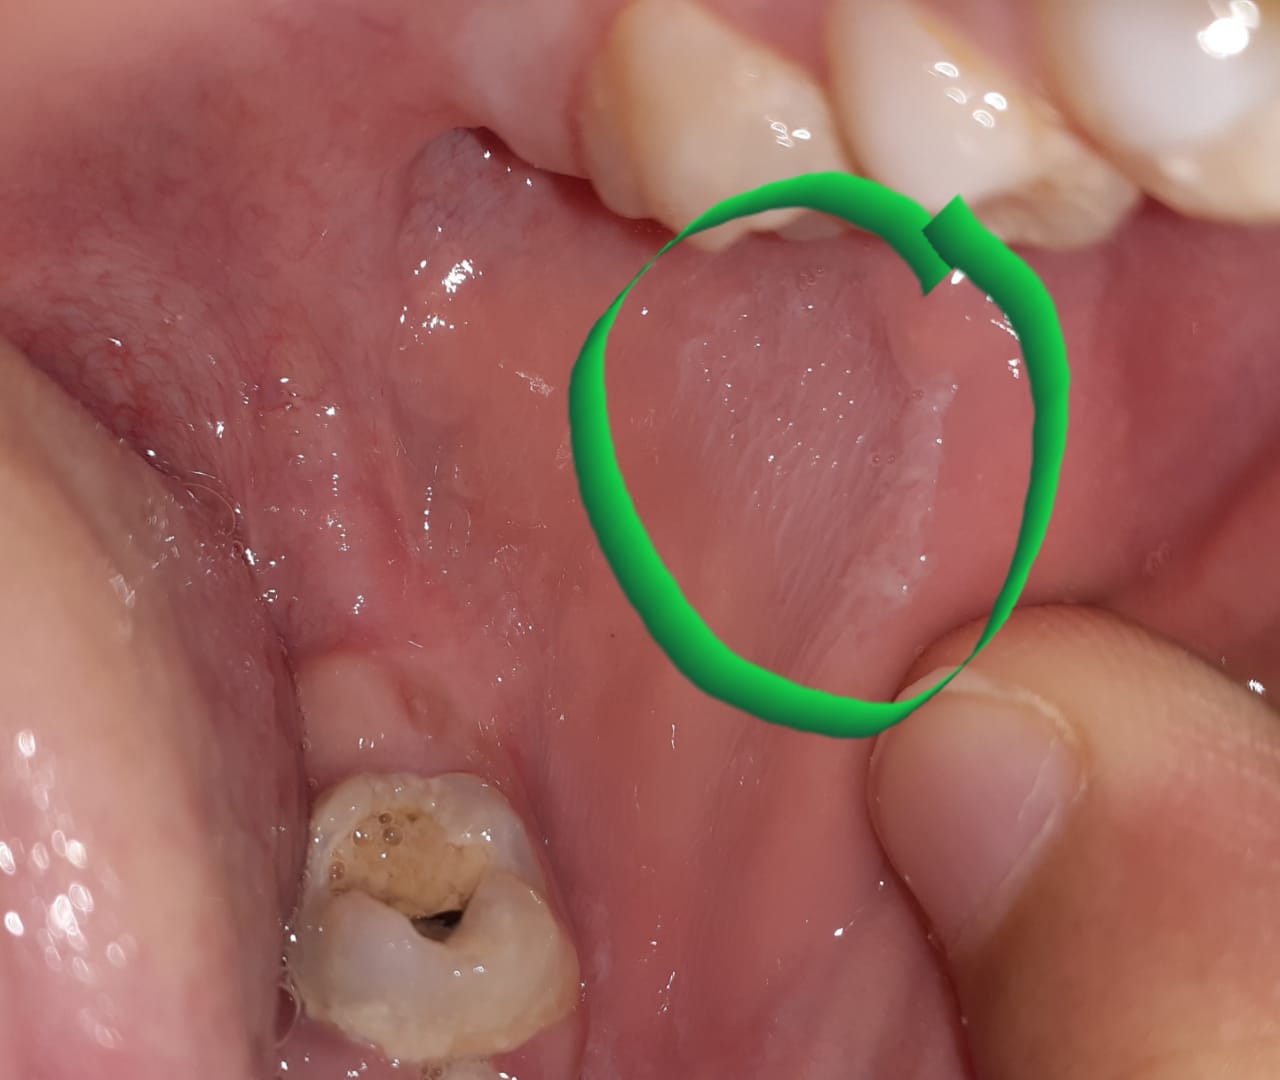

Hi! Any specialist In this group? I need a small help please My 10 years old son having this thing inside in his mouth , i dont know what to do and where to go Due to lock down. I can not go and see a doctor so if someone knows about it plz help

It's an abrasive lesion on the cheek most probably due to the lower molar which has Caries and sharp edges..